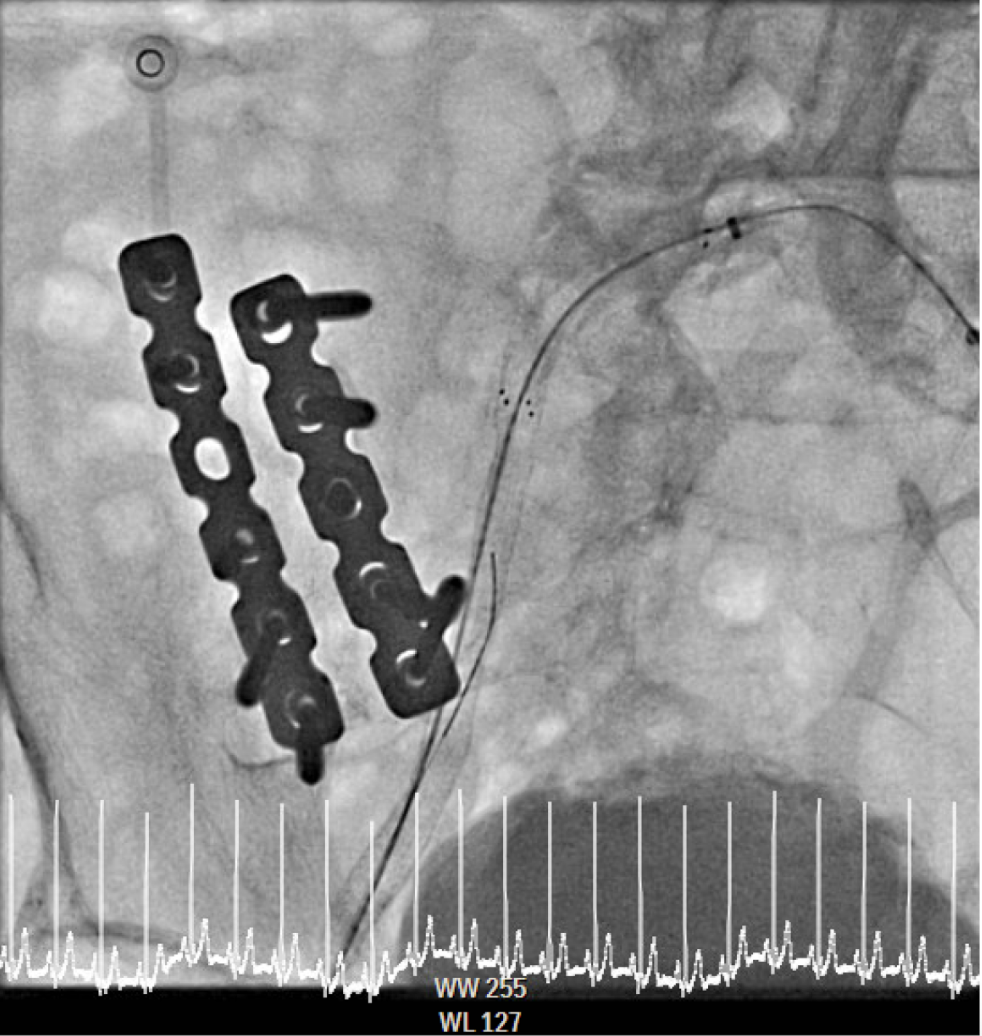

The procedure utilized a hybrid retrograde and antegrade approach. Retrograde access was established via a micropuncture kit under angiography guidance into the distal Superficial Femoral Artery (dSFA), but wiring attempts failed due to an intervening aneurysm, necessitating a switch to the antegrade route from the left brachial artery. A wire escalation technique, assisted by a microcatheter, successfully crossed the extensive CTO, and was met with retrograde microcatheter and externalized via the dSFA puncture site (retrograde access), establishing through-and-through wire access. Following initial balloon predilation and IVUS confirmation of diffuse thrombus, extensive angioplasty was performed. Definitive treatment involved deploying multiple overlapping GORE¢ç VIABAHN¢ç Endoprosthesis diameters (from 6mm to 8mm) from the dSFA proximally to the pEIA via left femoral access, effectively treating the long occlusion and excluding the aneurysm. A COOK Zilver Flex iliac stent reinforced the proximal landing zone. The stented segment was rigorously post-dilated up to 12 atm. The procedure concluded with a Drug-Eluting Balloon (DEB) PTA (BOSTON Ranger Paclitaxel-Coated PTA Balloon Catheter) to the dSFA to mitigate restenosis in the non-stented region. Final angiography confirmed good flow without distal embolization.